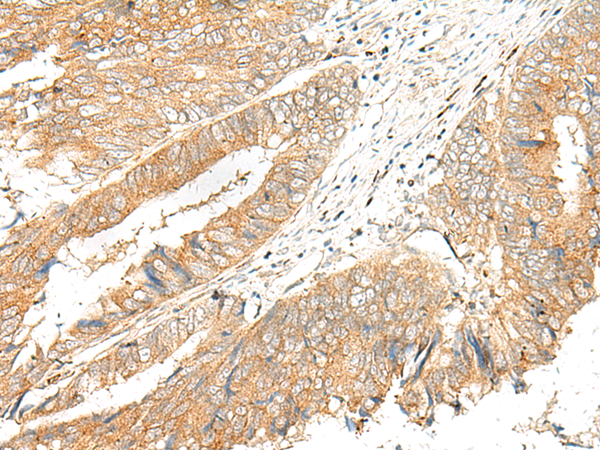

ELISA, IHC

IHC positive control:

Human cervical cancer and Human colorectal cancer